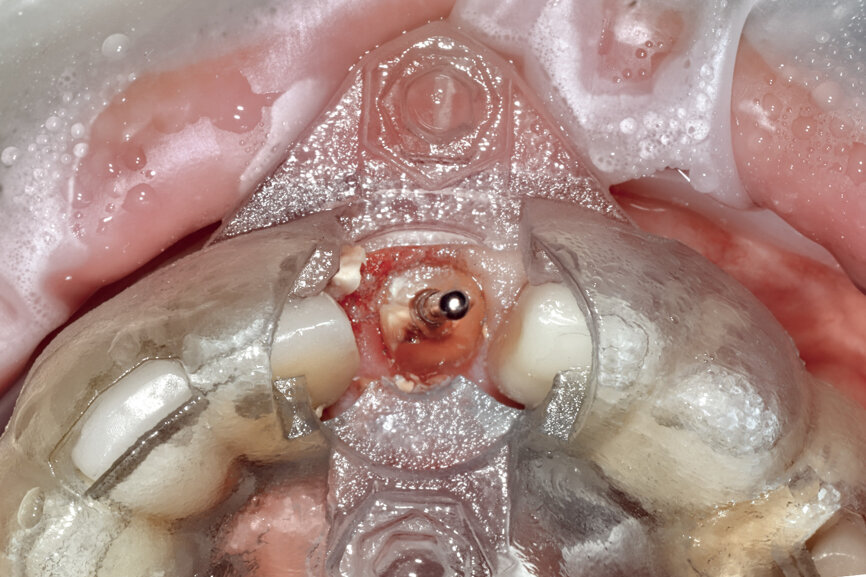

Fig. 23: The implant, seen prior to placement,

using the R2GATE surgical carrier for full-template guidance through the sleeveless guide.

Fig. 24a: Depth control and rotational positioning were accurately

confirmed with the notch indicator on the template corresponding with the insertion tool (a). The occlusal view illustrated that the anti-rotational internal

conical–hexagonal connection was positioned towards the facial aspect (b).

Prior to the guided drilling, a Gates–Glidden drill was used to remove any gutta-percha within the root. Utilising the tooth-borne template and the first insert, initial long shaper drills (IS1, IS2) were used to reach the apex of the root (Root Membrane Kit; Fig. 17). A periapical radiograph confirmed that the apex length had been reached and that all the gutta-percha had been removed (Fig. 18). The second insert had a metal cylinder that allowed for the long, round diamond drills to shape the root into the desired crescent shape (Fig. 19a). The insert was removed to access the palatal root (Fig. 19b). Using appropriate instrumentation such as periotomes, elvatomes or FRINGS forceps (both TBS Dental), the palatal root was carefully removed (Fig. 20). A periapical radiograph confirmed that the palatal root had been completely removed (Fig. 21). The next insert contained the final diameter to receive the guided sleeveless drills for osteotomy preparation (Fig. 22a). The osteotomy was prepared to avoid proximity to the remaining root fragment while leaving sufficient restorative space, as previously planned in the software simulation (Fig. 22b). Implant placement (AnyRidge, MegaGen) was facilitated by the R2GATE surgical carrier for full-template guidance at the appropriate torque values (Fig. 23). Depth control and rotational positioning were accurately confirmed with the notch indicated on the template to correspond with the insertion tool (Fig. 24).